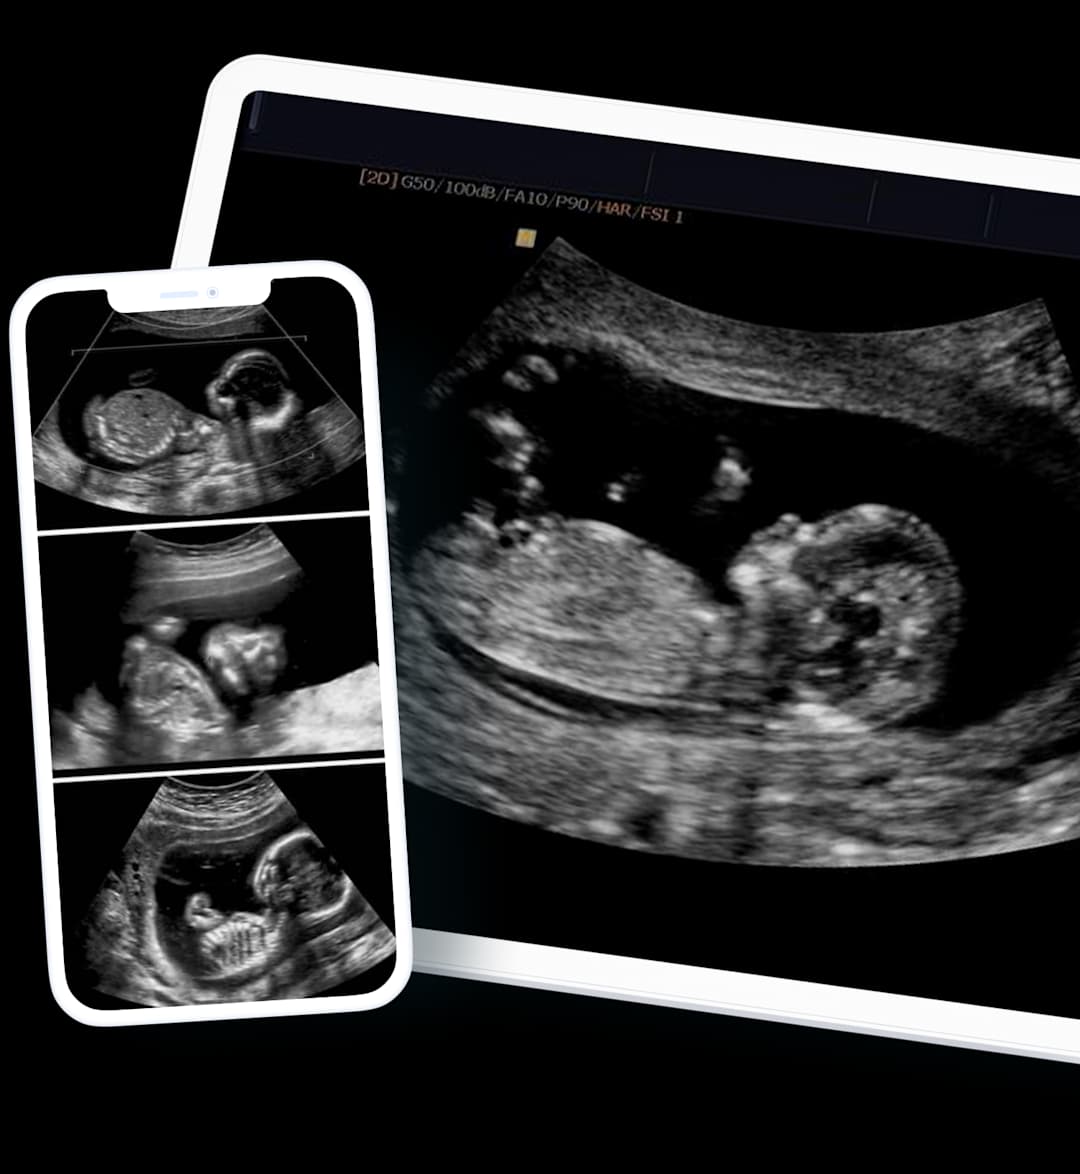

The images from your ultrasound with Harley Street Ultrasound Group will be available on the same day as your appointment via your computer or smartphone.

This empowers you to share your results with your trusted healthcare professional of your choice.

We can provide scan images directly to your smartphone, often on the same day following your appointment. Gain the peace of mind and insight you need, without delay.

Same-Day Results

Timely & Efficient

Share with your Doctor